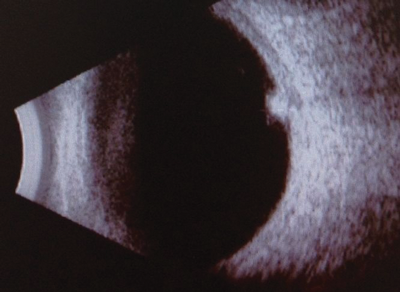

On examination, visual acuity was 6/6 in the right and 6/6 in the left. Ocular movements were full, there was no diplopia in any position of gaze. Anterior segment examination was normal with the pupils reacting equally to light on both sides. On dilated ophthalmoscopy the right retina was normal. The left retina revealed an elevated pigmented lesion over the optic disc. The lesion was measured using B scan ultrasonography and found to be 2.4mm x 1.7mm. The clinical appearance of the lesion was consistent with a diagnosis of melanocytoma.

Figure 2: B scan of optic disc melanocytoma.

Diagnosis is based mainly on clinical appearance. B-scan helps to measure the lesion and monitor its growth. Fundus fluorescein angiography and indocyanine green angiography are of limited value due to the intense pigmentation of the lesion [3].